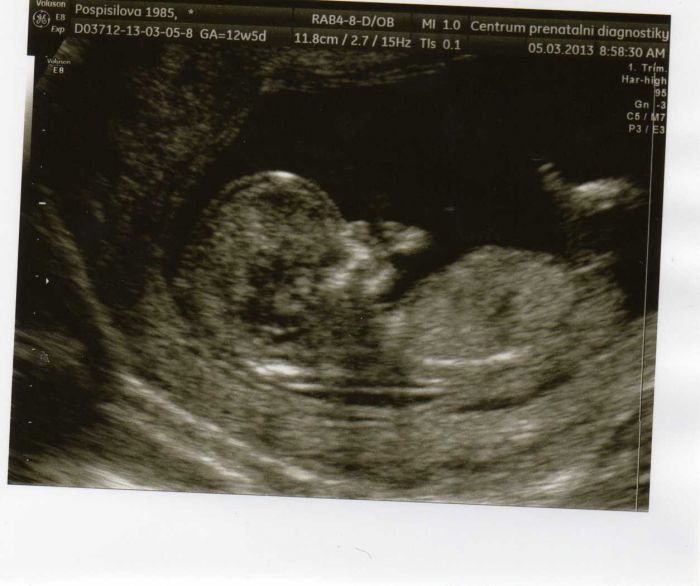

Autor: ivet :-) 9.3.2013 v 09:37

juuuchůů

seznam te se holky,to je naš malej koblížek

omlouvam se za kvalitu je to focene z webky,jinak mi to nešlo vložit